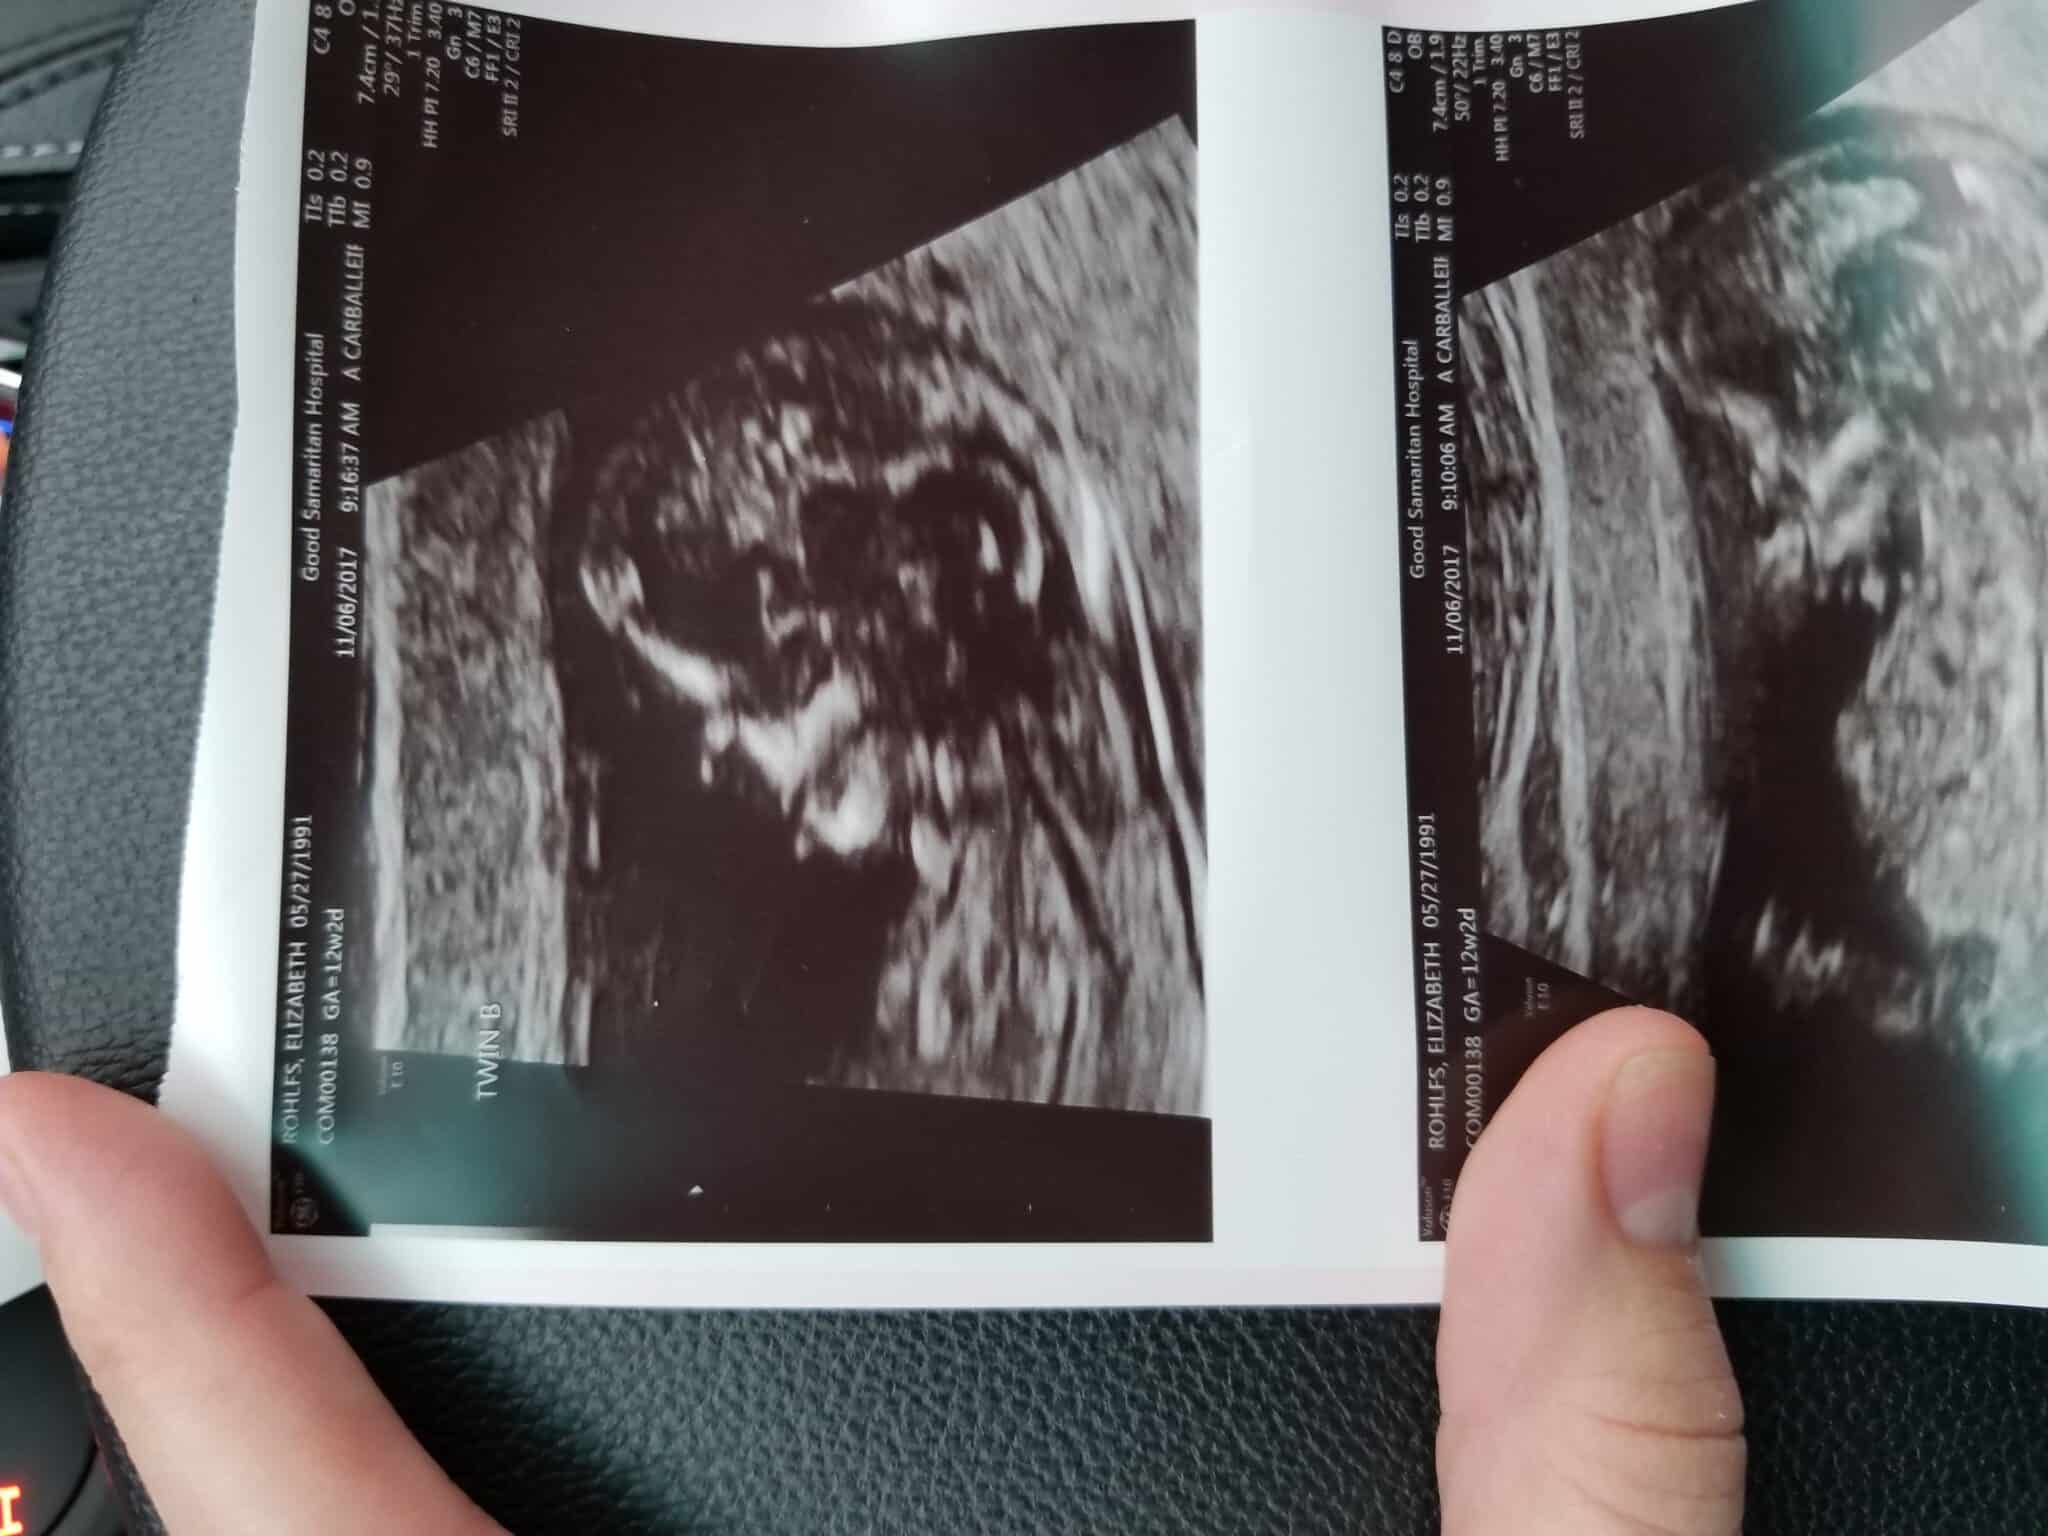

Ultrasound Photos at 12 Weeks Pregnant With Twins